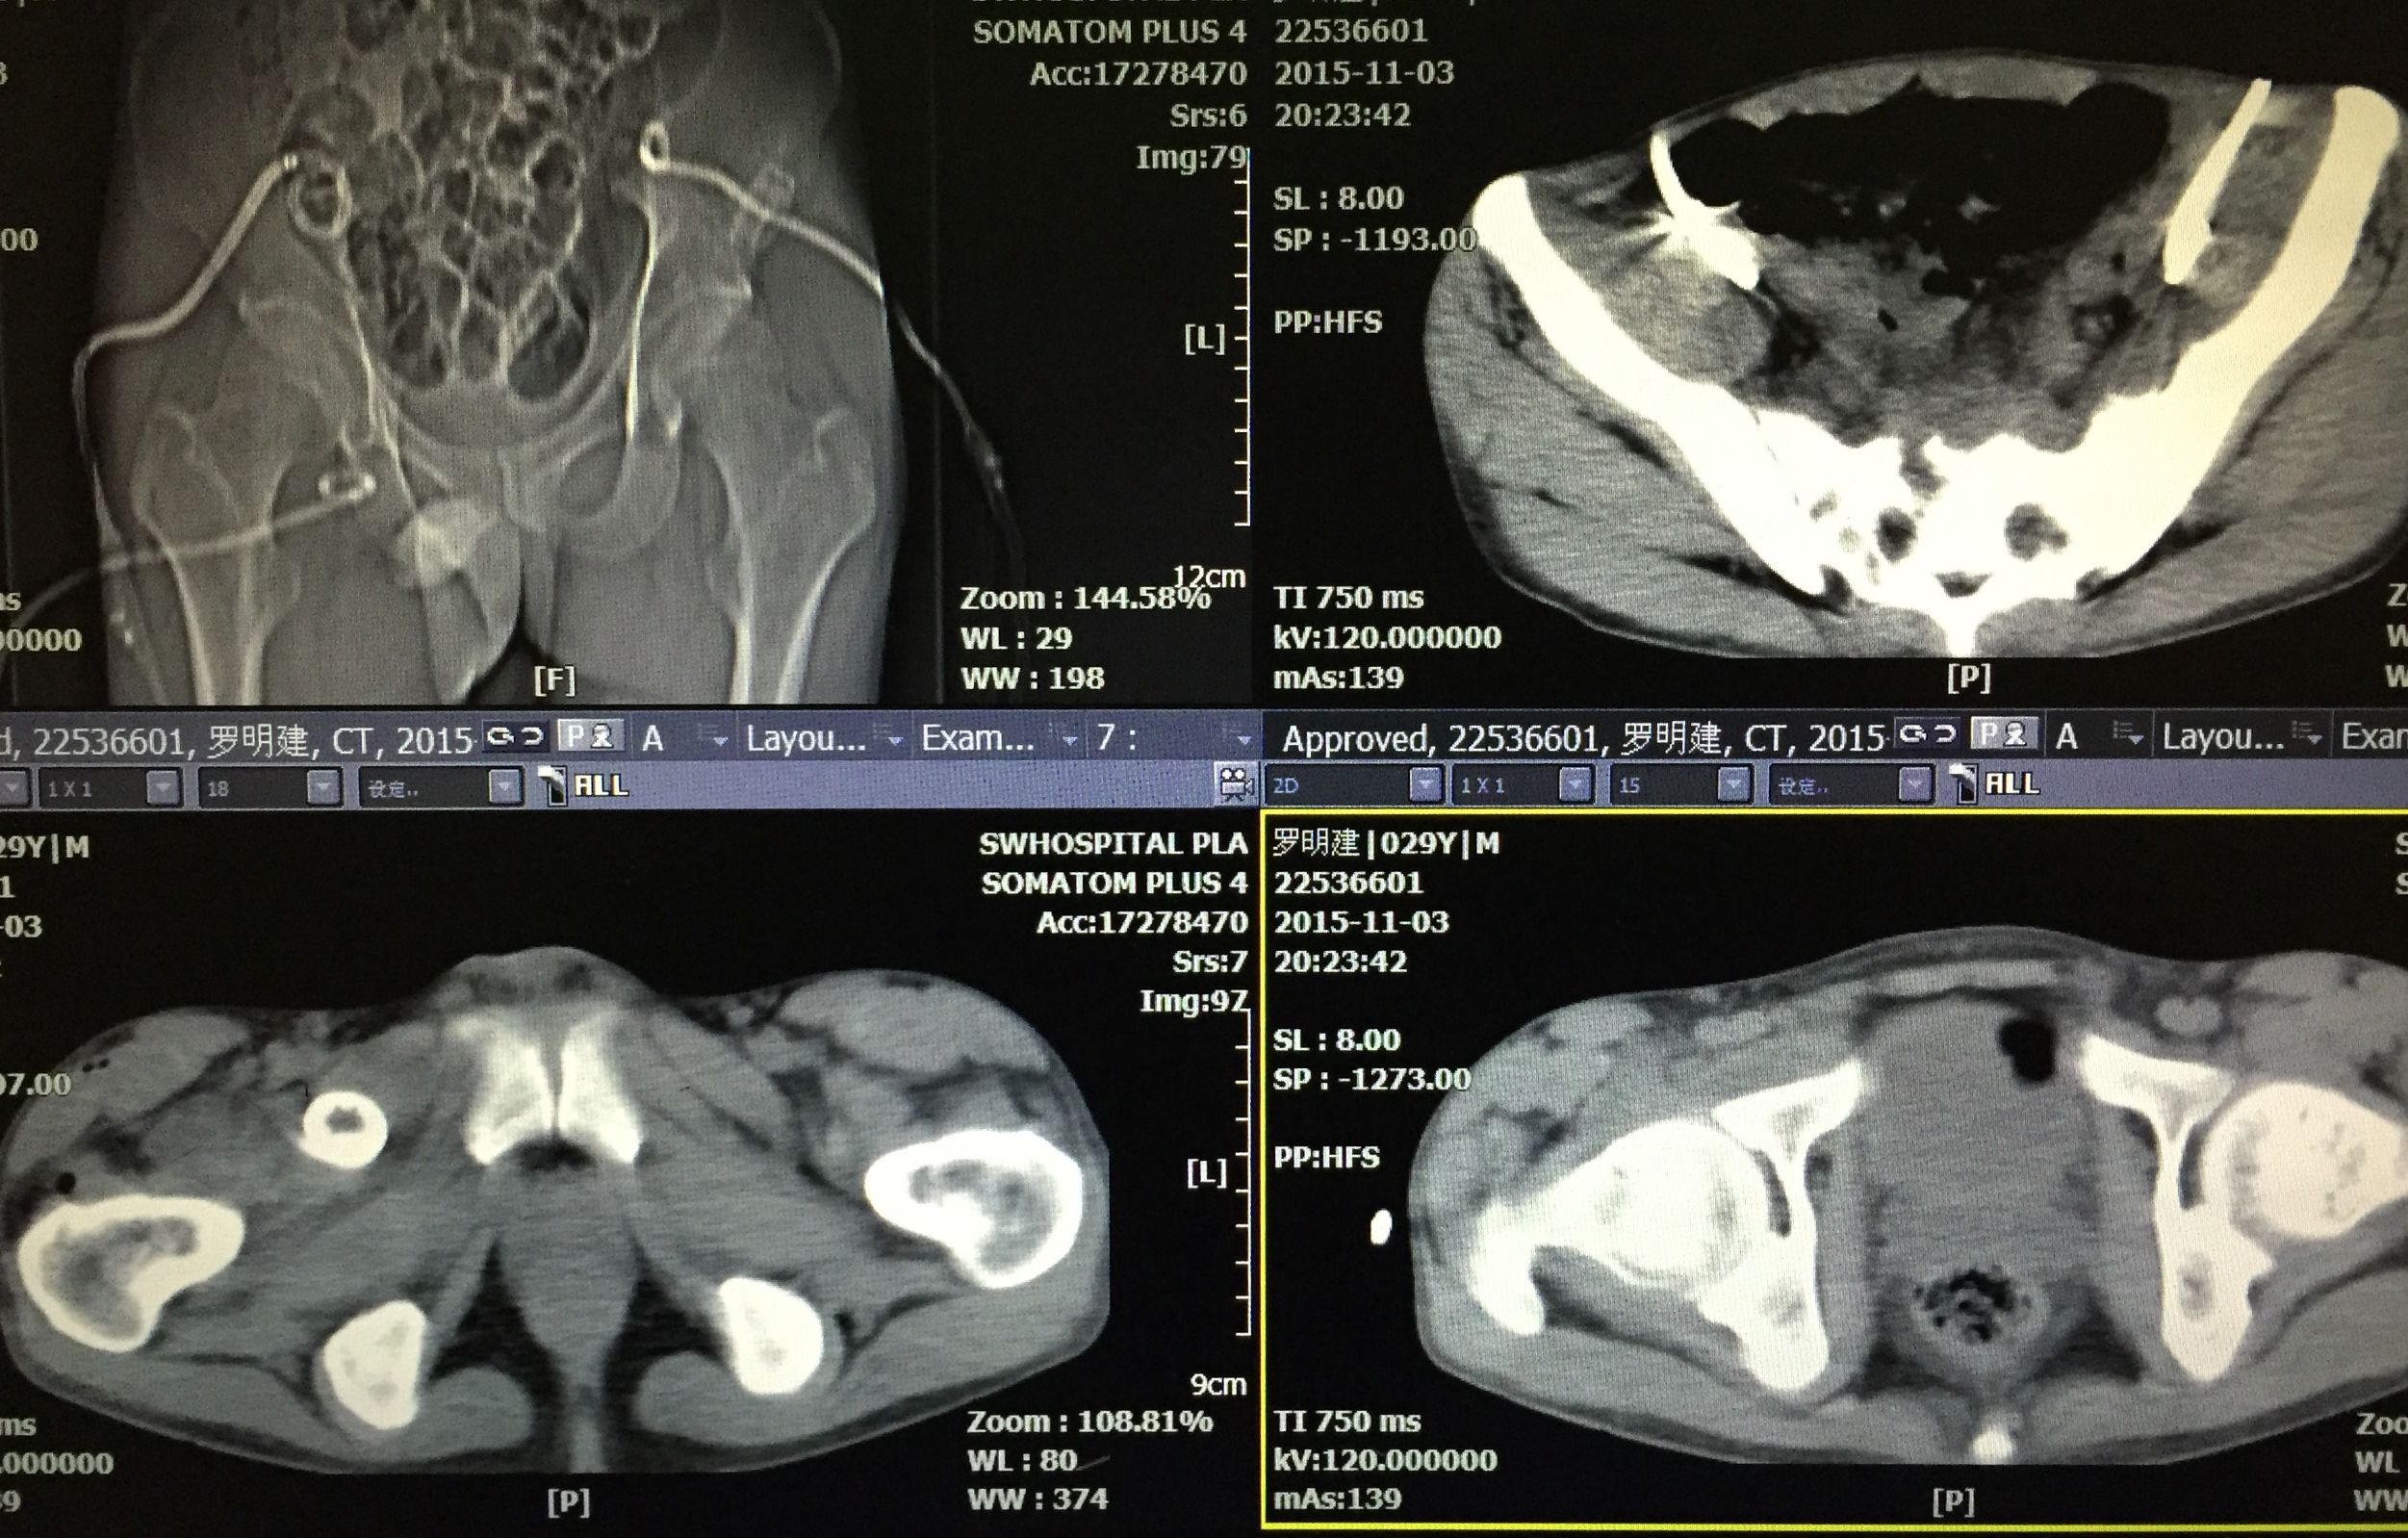

病例分享:2

患者 29岁 盆腔及大腿根部多发结核脓肿(如图)

治疗方案充分穿刺置管引流+抗痨治疗

在门诊进行CT引导下穿刺引流术,植入五根引流管(如图白色条状物)

植入一月后,拔出两个引流管,剩余三根引流管仍有脓液溢出。

三月后患者全部拔出引流管。继续抗痨治疗